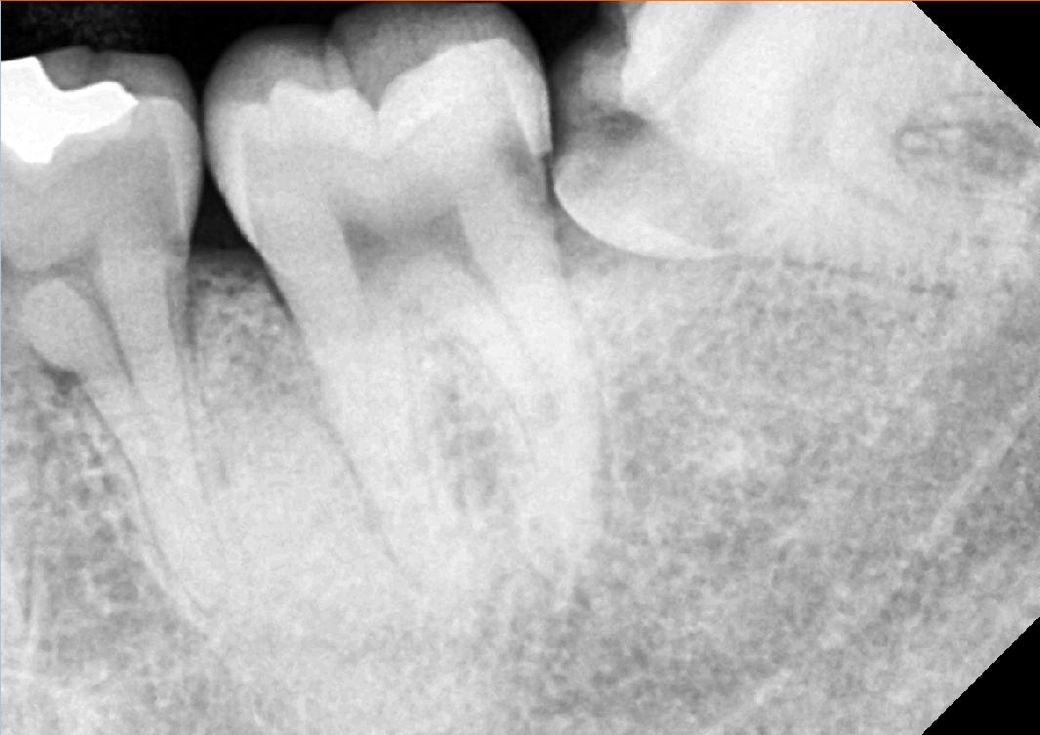

3.1개월후 직장때문에 B치과를 방문에서 오른쪽 사랑니 발치전에 x레이 찍으며 a치과에서 치료받은 어금니를 말하며(왼쪽사랑니 발치전 맞다은 곳) 왜 이곳까지 인레이 치료받지 않았냐 라고하셨습니다.( X레이상 으로 제가봐도 검게 파여있는부분이 있습니다)

4.이에 다시 A치과에 가서 인레이치료가 된것이 맞냐 라고 물으니 삭제를 최소한으로하고자했다며 f/u하면서 지켜보던지 아님 크라운을 하던지 라고하셨는데... 제생각엔 2~3개월만에 크라운얘기가 나올정도면 치료가 잘못된게 아닌지 생각이듭니다.

6.치료 전 사진

7.치료 후 사진

• 1번 째 사진

사진으로 봤을 경우에는 인레이 치료를 하고 나서도 하방에 충치가 남아있는 것으로 보이긴 합니다.

경우에 따라서 방사선 투과성이 있는 재료를 충전했을 경우에 해당 부위가 비어 있는 것처럼 보일 수도 있습니다. 충치가 내부에 남아 있다면 인레이를 제거하고 크라운 치료 등을 하는 것이 좋을 수 있습니다. 치료비 환불 등에 대한 내역은 해당 치과에 문의를 해야 정확할 것으로 생각됩니다.

현재 치료 후 사진을 봤을때 씹는면만 충치제거하고 인레이가 접착되어 있고 옆면(인접면)은 충치가 그대로 있는 것으로 보입니다.